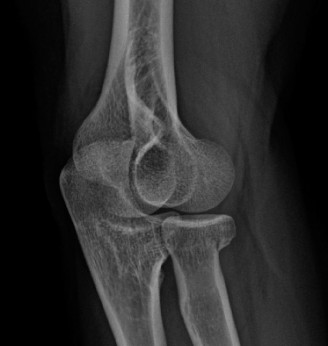

Standard orthogonal radiographs (anteroposterior and lateral) provide a baseline assessment of joint congruity, hardware position, and the gross extent of heterotopic ossification. However, a high-resolution Computed Tomography scan with three-dimensional reconstructions is the gold standard and an absolute requirement. The 3D CT scan allows the surgeon to precisely map the location of the heterotopic bone, distinguishing between extra-articular bridging bone and intra-articular osseous blocks. In our patient, the CT scan would explicitly define the posterior-medial mass and its relationship to the cubital tunnel and the medial column hardware.

In the setting of post-traumatic contracture, the joint capsule undergoes predictable pathologic changes. The anterior capsule typically thickens and contracts, limiting extension. Conversely, the posterior capsule, along with the posterior band of the medial collateral ligament, becomes fibrotic and limits flexion. Heterotopic ossification frequently develops within these capsular planes, particularly in the posterior-medial compartment between the olecranon and the medial epicondyle, directly adjacent to the ulnar nerve.

Attention is then directed to the posterior-medial heterotopic ossification mass. Using osteotomes, rongeurs, and a high-speed burr, the heterotopic bone is meticulously excised. Care must be taken to distinguish the heterotopic bone from the native medial epicondyle and the sublime tubercle to avoid iatrogenic destabilization of the anterior band of the medial collateral ligament.

Our patient presents with a severe Class IIC moving towards Class III given the rigid bony end-feel and profound multiaxial restrictions.